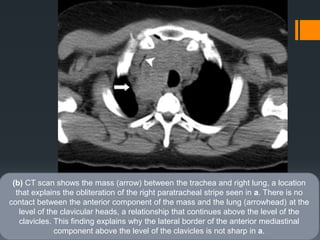

(b) CT scan shows the mass (arrow) between the trachea and right lung, a location

that explains the obliteration of the right paratracheal stripe seen in a. There is no

contact between the anterior component of the mass and the lung (arrowhead) at the

level of the clavicular heads, a relationship that continues above the level of the

clavicles. This finding explains why the lateral border of the anterior mediastinal

component above the level of the clavicles is not sharp in a.